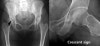

Pelvic AP view, Hip joint의 frog-lateral X-ray 검사를 해야합니다(보다 초기에 변화를 보이는 것은 frog leg lateral view).

초기에는 뚜렷한 이상 소견이 없다가 시간이 지나면서 점차 괴사부 외연을 따라 골음영이 증가하고, 괴사부 내 골음영도 불규칙하게 변합니다.

대퇴골두 연골하 골절이 있을 경우 crescent sign이 관찰되고, 괴사 부위가 함몰될 경우 골두가 납작해지면서 이차적인 퇴행성 변화가 초래됩니다(대퇴골두가 차차 붕괴되고 절구가 2차성 퇴행변화가 오면 퇴행성 고관절염과 감별이 어려울 수 있습니다).

X-ray : 대퇴골두 무혈성 괴사(Avascular necrosis of the femoral head)